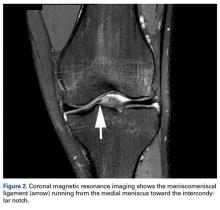

Radiographs taken the day of the first clinic visit showed no acute osseous abnormality. Magnetic resonance imaging (MRI) showed complete disruption of the proximal fibers of the ACL ( Figures 1, 2 ).

The medial and lateral menisci typically are separate fibrocartilaginous structures acting as a cushion for the knee, but normal variant connections between the structures have been described. These connections include the anterior transverse meniscal ligament, the posterior transverse meniscal ligament, and the medial and lateral oblique meniscomeniscal ligaments. 3 In the present case, a medial oblique meniscomeniscal ligament was identified. Its path between menisci was traceable on coronal and axial views. Video taken during arthroscopy also clearly showed its path and its relationship to other structures in the knee. To Dr. Flanigan’s knowledge, this ligament was not previously described with video. It is important to distinguish this ligament from a horizontal tear of the meniscus, given the potential for misinterpretation on MRI. A horizontal tear is a degenerative change that often occurs in older patients. Our patient was 18 years old at time of injury. In addition, the surface of his lower meniscus was smooth, whereas in a tear the edge is irregular and discontinuous. Dr. Flanigan prefers to leave this ligament intact unless resection would provide better visualization during arthroscopy. His reasoning is that the functional characteristics of the ligament are not well understood.